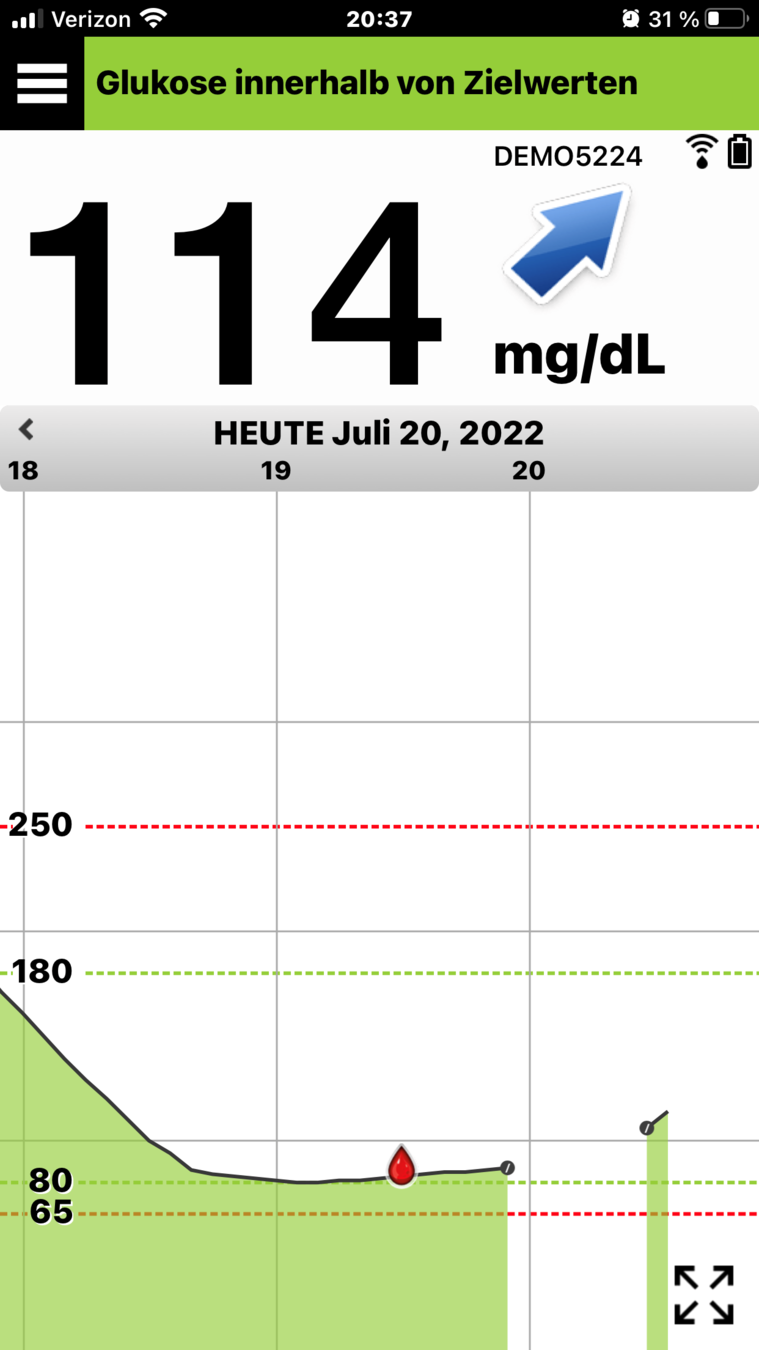

¡Le damos la bienvenida a su vida diaria con el sistema de MCG Eversense® E3! En esta presentación, descubrirá cómo puede ayudarle el sistema de MCG Eversense® a gestionar

su diabetes con más confianza.

Primero, revisemos la pantalla de inicio

Mi glucosa en la aplicación para móvil Eversense®.

PANTALLA DE INICIO MI GLUCOSA

Cuando abre la aplicación para móvil Eversense®,

se muestran principalmente su nivel

de glucosa actual y una flecha de tendencia.

PANTALLA DE INICIO MI GLUCOSA

Primero, revisemos la pantalla de inicio

Mi glucosa en la aplicación para móvil Eversense®.

En la parte superior derecha, puede ver

la intensidad de la conexión entre el transmisor y el sensor, y la carga de la batería que tiene

el transmisor.

PANTALLA DE INICIO MI GLUCOSA

Primero, revisemos la pantalla de inicio

Mi glucosa en la aplicación para móvil Eversense®.

Cuando abre la aplicación para móvil Eversense®,

se muestran principalmente su nivel

de glucosa actual y una flecha de tendencia.

Si ha activado la función No molestar o Perfil temporal, aparecerán los iconos correspondientes

en la parte superior izquierda.

PANTALLA DE INICIO MI GLUCOSA

Y, en la parte inferior, se encuentra el gráfico de tendencia de la glucosa.

Las líneas discontinuas rojas indican los niveles de alerta de glucosa alta y baja, y las líneas discontinuas verdes indican el intervalo objetivo.

Todos los eventos que introduzca en la aplicación (como una calibración, comida, ejercicio

o insulina) o las alertas que reciba, se mostrarán en el gráfico de tendencia con un icono.

PANTALLA DE INICIO MI GLUCOSA

Si ha activado la función No molestar o Perfil temporal, aparecerán los iconos correspondientes en la parte superior izquierda.

Puede consultar la sección Utilizar la aplicación para móvil en la Guía de consulta rápida del sistema de MCG Eversense® E3 en cualquier momento.

Con la MCG, puede ver de un solo vistazo:

Valor

de glucosa

INFORMACIÓN DE MCG ÚTIL

- cuál es su nivel de glucosa en sangre;

Flecha

de tendencia

- hacia dónde se dirige y con qué rapidez

Con la MCG, puede ver de un solo vistazo:

- cuál es su nivel de glucosa en sangre;

INFORMACIÓN DE MCG ÚTIL

Información reciente de tendencias

y alertas

- y las últimas 3 horas de datos de glucosa.

- hacia dónde se dirige y con qué rapidez

Con la MCG, puede ver de un solo vistazo:

- cuál es su nivel de glucosa en sangre;

INFORMACIÓN DE MCG ÚTIL